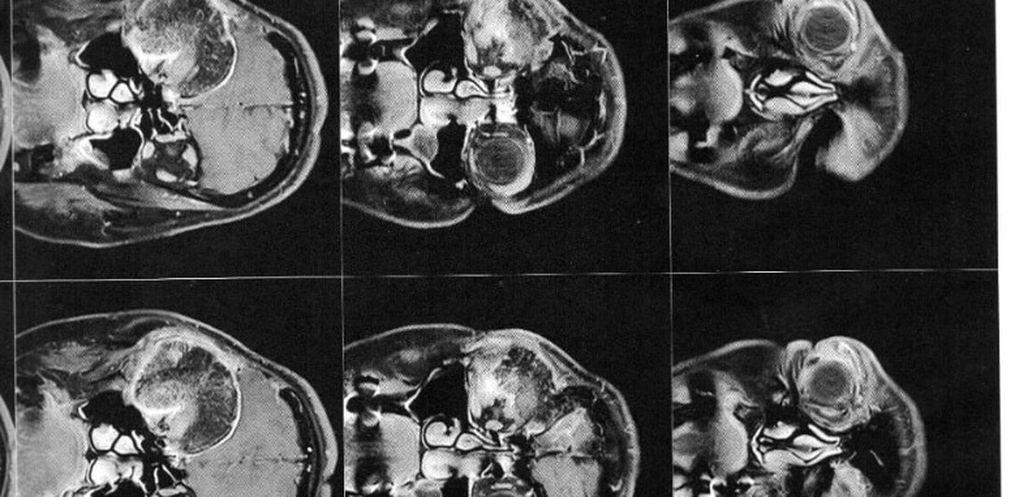

Então este médico solicitou exames de imagem (ressonância magnética e tomografia) para avaliar a situação, os quais foi constatado que o meningioma ainda está ali, e que continua empurrando o olho e se expandindo para outras áreas. Trata-se de um meningioma gigante (medindo 6 x 6,6 x 6 cm), que está localizado na placa do assoalho da fossa média e anterior.

Este outro profissional também disse que se tratava de um caso raro, e que ele não conseguiria resolver, afirmando que só existia um médico no Brasil que seria capaz de realizar a cirurgia dela com êxito. Então a encaminhou para o Dr. Feres Chaddad, referência nacional e internacional no campo da microcirurgia neurológica. Seu consultório fica em São Paulo/SP – a mais de 900 km de distância de Campo Erê/SC.

A cirurgia deverá ser feita de urgência, pois o meningioma continua se expandindo, e pode comprimir o olho esquerdo afetando a visão que lhe resta. Também pode comprimir outras partes do cérebro, ou pior ainda, causar a morte.

O médico também disse que será necessário realizar dois procedimentos cirúrgicos, um para retirada do tumor, e o segundo para realocar o olho para seu lugar e implantar a prótese onde o osso foi retirado.